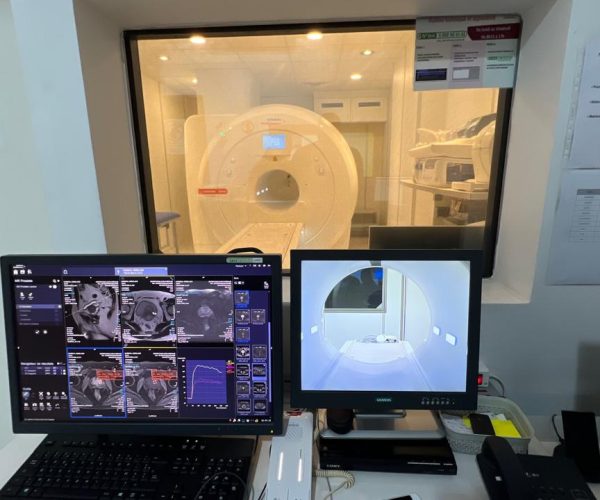

Matériel utilisé

• Magnetom Siempra 1,5 Tesla, Siemens

Pendant l'examen

• le patient s'allongé. Une antenne est placée au niveau de l'organe à visualiser puis il entre automatiquement dans l'appareil.

• Le patient peut se rassurer, il n'est pas seul : le personnel médical le voit et l'entend. En cas de problème, il est muni d'une poire qui permet d'appeler et de le faire sortir par une simple pression.

• Par ailleurs, la machine étant bruyante, nous proposons au patient un casque qui peut diffuser de la musique